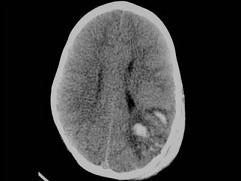

问题 男,3岁,头颅被球击中,请结合CT图像,最选择可能的诊断是 ( )

选项 A、动脉瘤破裂出血 B、血管畸形 C、脑结核 D、脑挫裂伤血肿形成 E、高血压性脑出血

答案 D